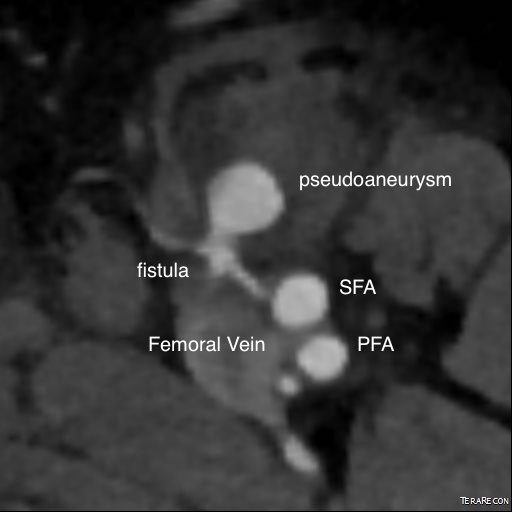

wide avf and pseudo

On examination, he had this well circumscribed indurated hematoma of hard boiled egg size with tenderness. There was a bruit on auscultation. Duplex showed a small chamber of flow adjacent to the proximal superficial femoral artery emptying into the femoral vein. Doppler in the common femoral vein showed relatively high fistula flow, and this is reported to be associated with failure of thrombin injection. CTA (top) demonstrated flow of contrast from femoral artery to vein through a pseudoaneurysm chamber that laid between. Angulation to an axial orientation showed this better (below).

axial AVF

Contrast flows from femoral artery (right) to the fistula chamber, then into the femoral vein.

axial CTA avf pseudo

Axial MPR